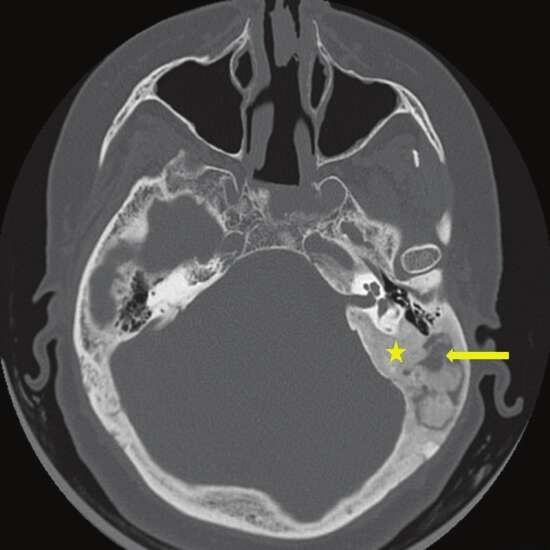

HRCT Temporal Bone Axial is also referred to as high-resolution computed tomography of the temporal bone to visualize the detailed structure of the lower part of the skull and its surrounding tissue in the axial plane.

High-resolution computed tomography is an imaging technique that scans various views of the skull’s temporal region and its related structures. The scan is also known as high-resolution CT of the temporal bone.